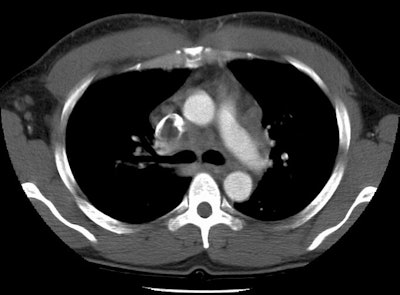

Pulmonary emboli in a lymphoma patient with SVC thrombosis

This case nicely demonstrates clot in both the superior vena cava and the left lower lobe segmental pulmonary arteries. There is also a small clot in a left upper lobe segmental vessel.